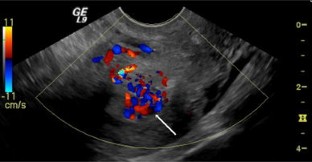

Fig. 1